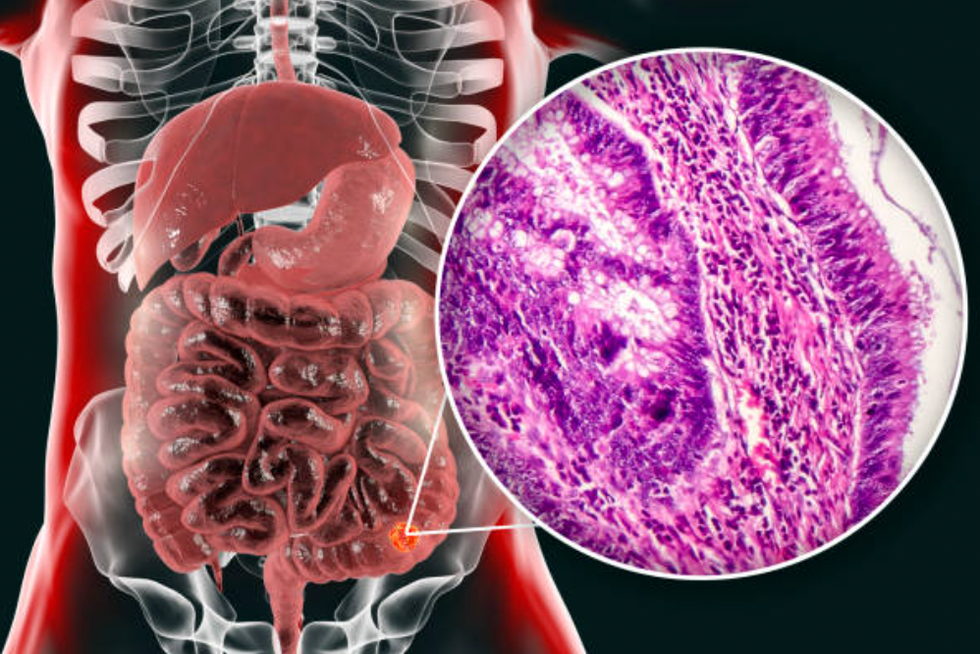

The researchers followed 101 patients in the US who were diagnosed with microsatellite stable metastatic colorectal cancer (MSS mCRC), the most common type of bowel cancer.

Until now, immunotherapy has only been shown to work on patients with another type of bowel cancer known as specific mismatch repair deficient (dMMR) tumours, which is rarer.

Close to 43,000 people are diagnosed with bowel cancer every year in the UK, with around 85 percent classed as microsatellite stable (MSS).